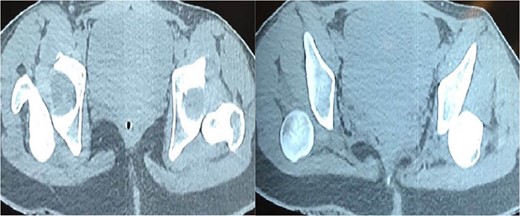

CT-Scan show bilateral posterior hip dislocation without evidence of fracture or articular fragments.